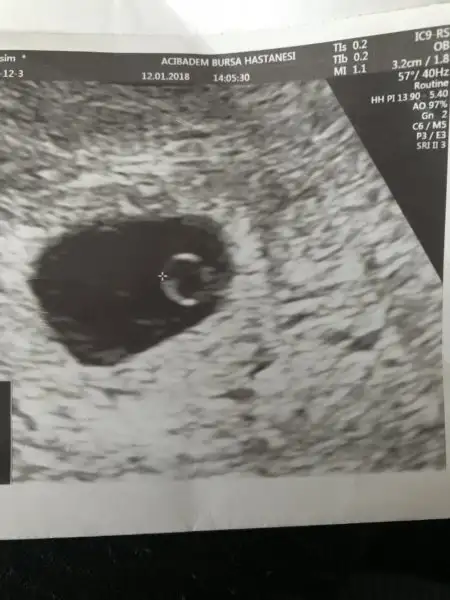

Ara canım mutlaka,vajinal kullanmak çok daha rahat. Dün sana kese fotosu koyacaktım dışardayım diye koyamadım. Şimdi koyayım bak. 1. Foto kesenin ilk hali, 2. Foto fasulyeye dönmüş hali.

Ben Eskişehir Acıbademde yaptırıcam takip ve doğumumu. Burada aşılamamı yapan doktorum var ona gidicem. 120 tl idi aralıkta zam gelmiştir ocakta sezeryan doğumda 5000 tl imiş sanırım. İlk muayene için tüp bebek yaptırdığım Bursa Acıbademdeki dr çağırdı ilk muayene tedavi ücretine dahil değilmiş orada 350 tl vericez sonra burada devam